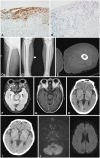

Embolic Infarction with Subdural Hemorrhage in Erdheim-Chester Disease